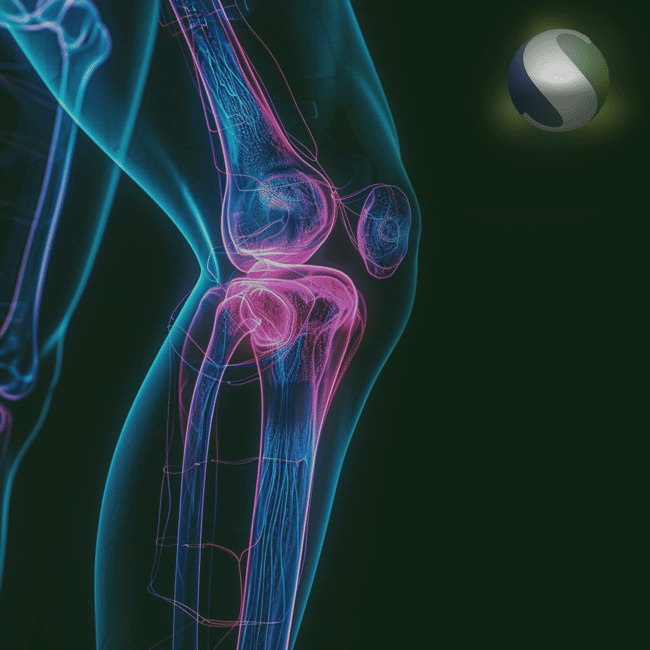

PRÓTESES

A Orthoset oferece produtos voltados à reconstrução e substituição articular, especialmente para joelho, quadril e ombro. Nossas soluções combinam inovação, durabilidade e desempenho biomecânico, proporcionando aos profissionais de saúde a confiança necessária para alcançar os melhores resultados cirúrgicos. Com foco na restauração da mobilidade e da qualidade de vida, trabalhamos com marcas parceiras que seguem rigorosos padrões internacionais de qualidade.